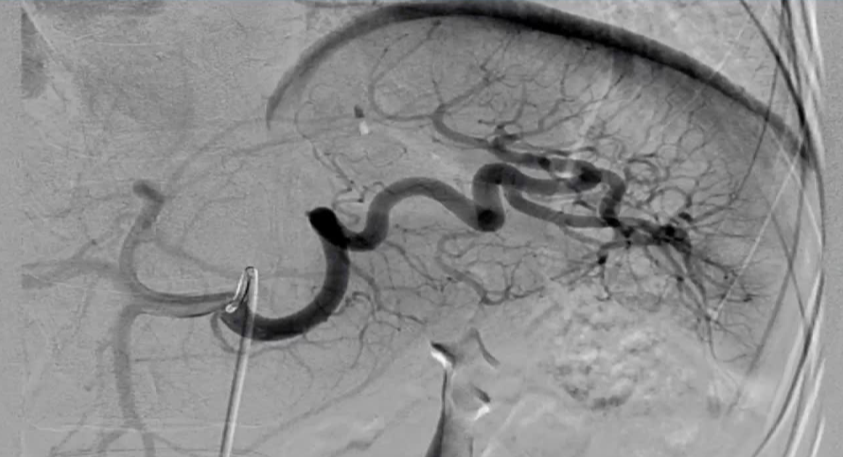

创伤患者的近端和远端脾栓塞

近端栓塞 |

- 多发性损伤 CT 显示撕裂 没有 造影剂外溢 |

脾实质灌注压力下降 |

更短的 操作时间,降低 辐射剂量 |

无法轻易地规划未来栓塞术 |

弹簧栓子和血管塞 |

弹簧栓子移位(<1%) |

远端栓塞 |

伴有血管损伤的患者 |

特定受损血管的选择(超选择行) |

选择性栓塞 |

增加操作时间和更大的脾梗塞 |

弹簧栓子和栓塞微粒 |

脾梗死或脾脓肿形成 |

弹簧栓子的位置:胰大动脉和胰背动脉之间